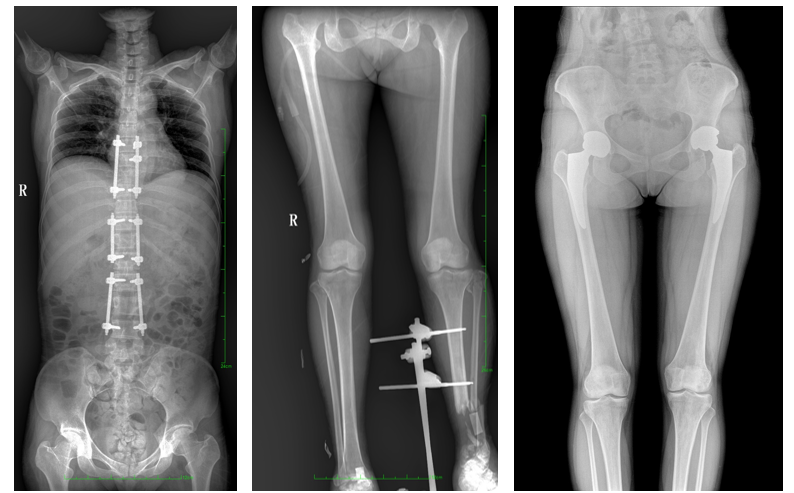

普愛醫(yī)療自主研發(fā)的一款數(shù)字化X光機(jī)——PLX8600大視野平板動(dòng)態(tài)DR,擁有43cm*86cm超大有效視野,可一次性拍攝全脊柱、雙下肢的影像視野。使全脊柱及雙下肢能夠得到完整清晰的成像,為臨床在脊柱側(cè)彎畸形和下肢骨關(guān)節(jié)病變診斷、治療方案制定及治療后復(fù)查提供精準(zhǔn)的測量。

數(shù)字化X光機(jī)影像

除常規(guī)靜態(tài)攝影外,PLX8600具備動(dòng)態(tài)透視和點(diǎn)片功能,透視采集功能可支持大視野、多角度的可視化觀察。通過可視化的動(dòng)態(tài)影像,配合點(diǎn)片功能,能夠很好的觀察復(fù)雜部位病灶,有效的抓取關(guān)鍵幀,降低患者多次攝片的概率。如:全脊柱狀態(tài)評估、長骨關(guān)節(jié)活動(dòng)度、下肢靜脈造影瓣膜功能評估、消化道功能評估、脊髓造影等更多大視野臨床應(yīng)用。